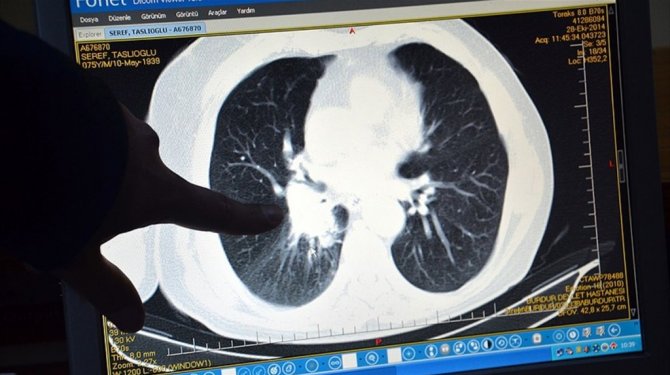

Türkiye'de erkeklerde en sık akciğer kanseri görülüyor

ERKEKLERDE AKCİĞER, KADINLARDA MEME KANSERİ İLK SIRADA